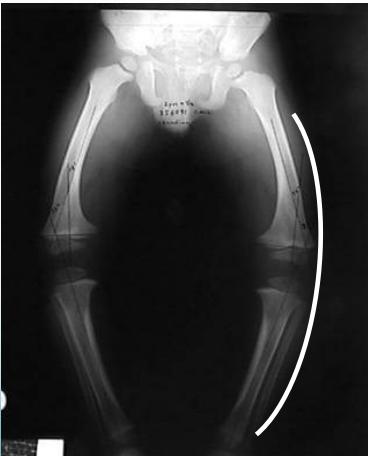

Radiological Assessment

Indications: X-ray when severe or possibly pathologic

Recommended Views:

- Standing AP film: Long film (hips to ankles) with patellae directed forwards

Radiological Parameters to Assess:

- Medial Physeal Slope

- Femoral-Tibial Axis